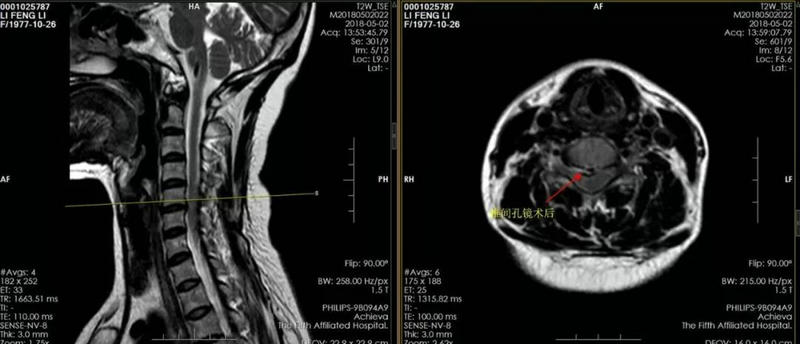

▲ 术后MRI:椎间盘孔镜治疗后椎间盘切除,术后症状明显改善。

但是真正的医者总会尽量把困难留给自己,把健康留给患者。“舒适无痛苦、治愈有尊严”绝不仅仅是脊柱骨病科的一句口号。张长江教授及团队直面挑战,完善所有检查后于李医生入院第二天,成功为其实施颈椎椎间孔镜下椎间盘切治疗。手术历时60分钟,出血不到5ml,切口仅为4mm,绝不影响其美观。微创手术的效果确实不一样。术后当天李医生就能下床活动,不用身上插满各种仪器、管道,避免了尴尬,获得了尊严。术后第六天李医生顺利出院,开心的走出科室大门。